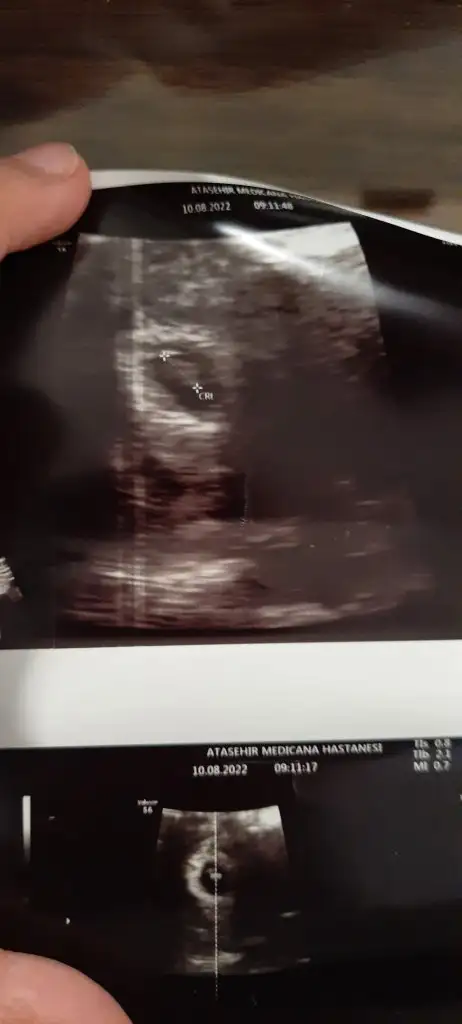

Doktora gittim kızlar. 11. Haftayla uyumlu çıktı ama tarihi degistirmicem. Zaten marta kayiyorum öyle

Burun kemiği baktı var dedi. 15 gün sonra tekrar çağırdı ufak bir kanama alanı varmış ama sorun olacağını sanmıyorum dedi. Kan gelirse korkma progestan başlarsın kan gelirse dedi. Ağır kaldırma ayaklarını uzatarak otur dedi. Yürüyüş yapabilirsin dedi

Veeeeeeeeee kız gibi duruyor dedi

Evet canım 4 cm çıktı bebiş 11 hafta tam

15 gün sonra geldiğinde net belirleriz dedi canım 22sine randevu verdioh maşallah kocaman olmuş ablası olucak buranın

Karından kuzum artık vajinal bakılmaz şükür kocamanlar artıkA a hadi gözün aydın kuzumm masallah bebişe büyüsün saglıkla onu nasıl görüyo canım vajinal mı bakıyolar karından görülüyormı

Sana atayım da bak ben anlamıyorum canım